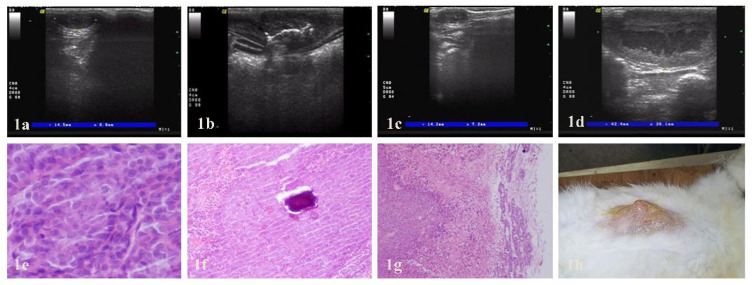

背景:本研究旨在探讨高频超声(US)对兔VX2乳腺肿瘤组织形态和血流动力学的影响,以及超声引导下经皮微波凝固(PMC)治疗兔VX2乳腺肿瘤的有效性和安全性。方法:20只VX2荷瘤兔,采用彩色多普勒超声检查肿瘤的生长特征,包括回声、大小、血供及血流动力学参数,每周1次,连续6周。随后,在随机分配的10只VX2荷瘤兔(另外10只作为对照)中进行us引导PMC。获得消融后的超声图像并进行分析。3只双VX2肿瘤兔在消融第0、1、4周作病理观察。通过肿瘤生长情况、体格检查、生存时间、肿瘤生存率、转移情况及组织病理学等指标评价治疗效果。结果:超声监测显示肿瘤生长速度为463.09%,第2 ~ 3周,在实时超声引导下行PMC。经微波消融后,部分肿瘤在第8周明显缩小或无法检测到。此外,美国没有检测到流量信号。治疗组和对照组2、3个月生存率分别为100%、70%和10%、0%,转移率分别为10%、30%和90%、100% (p结论:超声显像监测兔VX2乳腺癌的增殖和转移,超声引导下经皮微波消融治疗兔乳腺癌是一种安全、有效、微创的治疗选择,具有潜在的临床适用性。

Methods: Twenty VX2 tumor-bearing rabbits were assessed using color Doppler ultrasound for tumor growth characteristics including echo, size, blood supply and hemodynamic parameters once a week for six weeks. Subsequently, US-guided PMC was performed in randomly assigned ten VX2 tumor-bearing rabbits (the other ten as controls). US images after ablation were obtained and analyzed. Three rabbits with double VX2 tumors were used as pathological observation at weeks 0, 1, and 4 of ablation. The therapeutic efficacy was evaluated by tumor growth, physical examinations, survival time, survival rate and metastasis of tumors and histopathology.

Results: Ultrasound monitoring indicated that the tumor growth rate was 463.09% at the 2nd to 3rd weeks, and PMC was performed during this period under real-time US guidance. After microwave ablation, some tumors were greatly reduced or undetectable at week 8. Moreover, no flow signals were detected by US. The survival rates at 2 and 3 months in the treatment group and control group were 100%, 70% and 10%, 0%, respectively, while the metastatic rates were 10%, 30% and 90%, 100%, respectively (P<0.05).